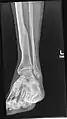

X-ray avulsion fracture of the summit of the left lateral malleolus.